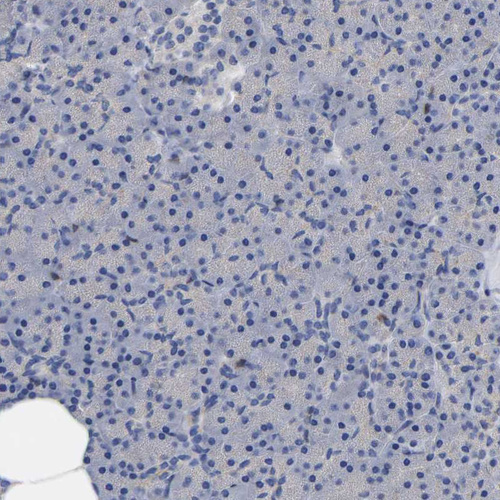

Immunohistochemical staining of human lymph node shows strong cytoplasmic positivity in non-germinal center cells.